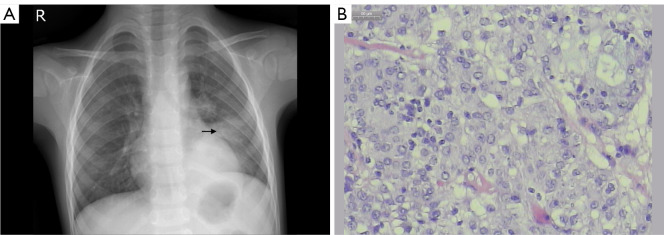

Pediatric pulmonary mucoepidermoid carcinoma in a 5-year-old patient.

1例5岁儿童肺黏液表皮样癌。